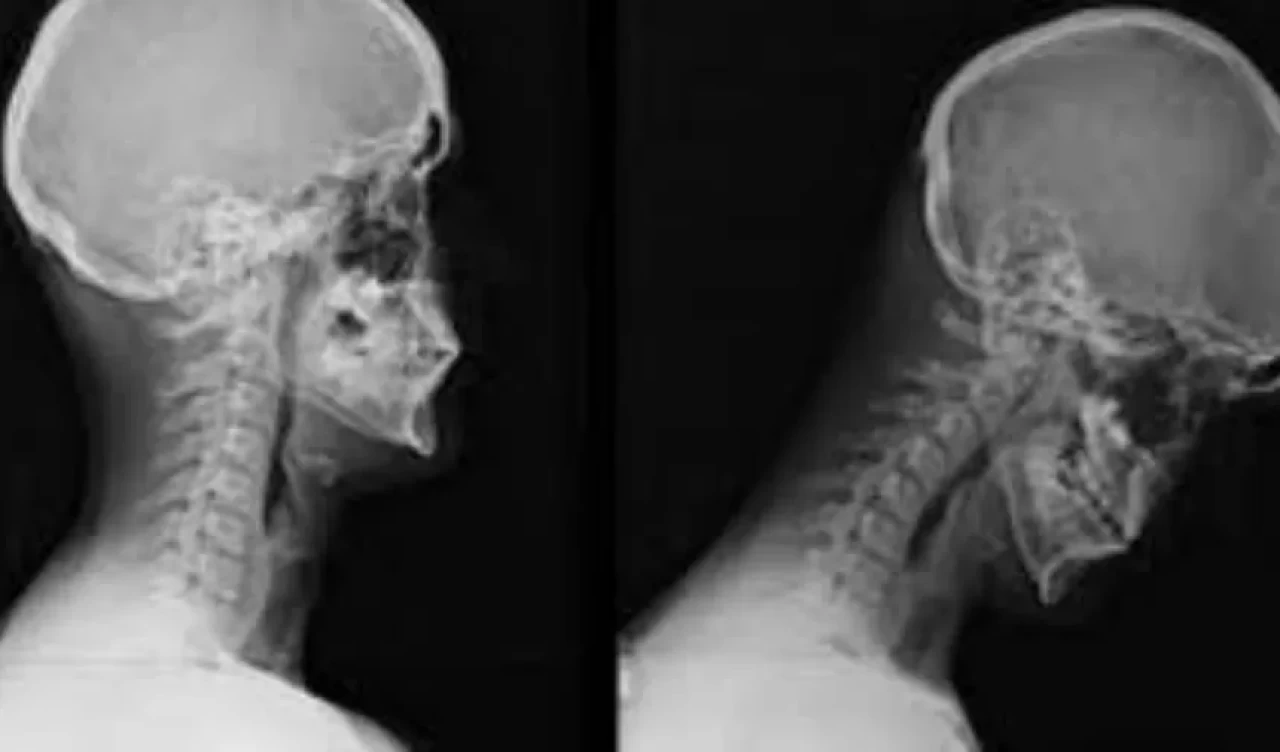

Cep Boyun Sendromu (Text Neck), özellikle akıllı telefonlar, tabletler ve bilgisayarların aşırı kullanımına bağlı olarak gelişen bir postür bozukluğudur. Uzun süre başın öne eğilmesiyle boyun, omuz ve sırt bölgesinde ağrı, kas gerginliği ve postür bozukluklarına neden olan bu sendrom, günümüzde teknoloji bağımlılığının yaygınlaşmasıyla daha fazla kişiyi etkiliyor. Peki, cep boyun sendromunun belirtileri nelerdir ve nasıl önlenebilir? Uzmanlar bu soruları yanıtladı.

Cep boyun sendromunun başlıca belirtileri, boyun, omuz ve sırt bölgesinde ağrı ve sertlik, baş ağrıları, hareket kısıtlılığı, elde uyuşma ve karıncalanma gibi semptomlardır. Bu belirtiler zamanla daha da şiddetlenebilir ve omurga eğrilikleri ile postür bozukluklarına yol açabilir.